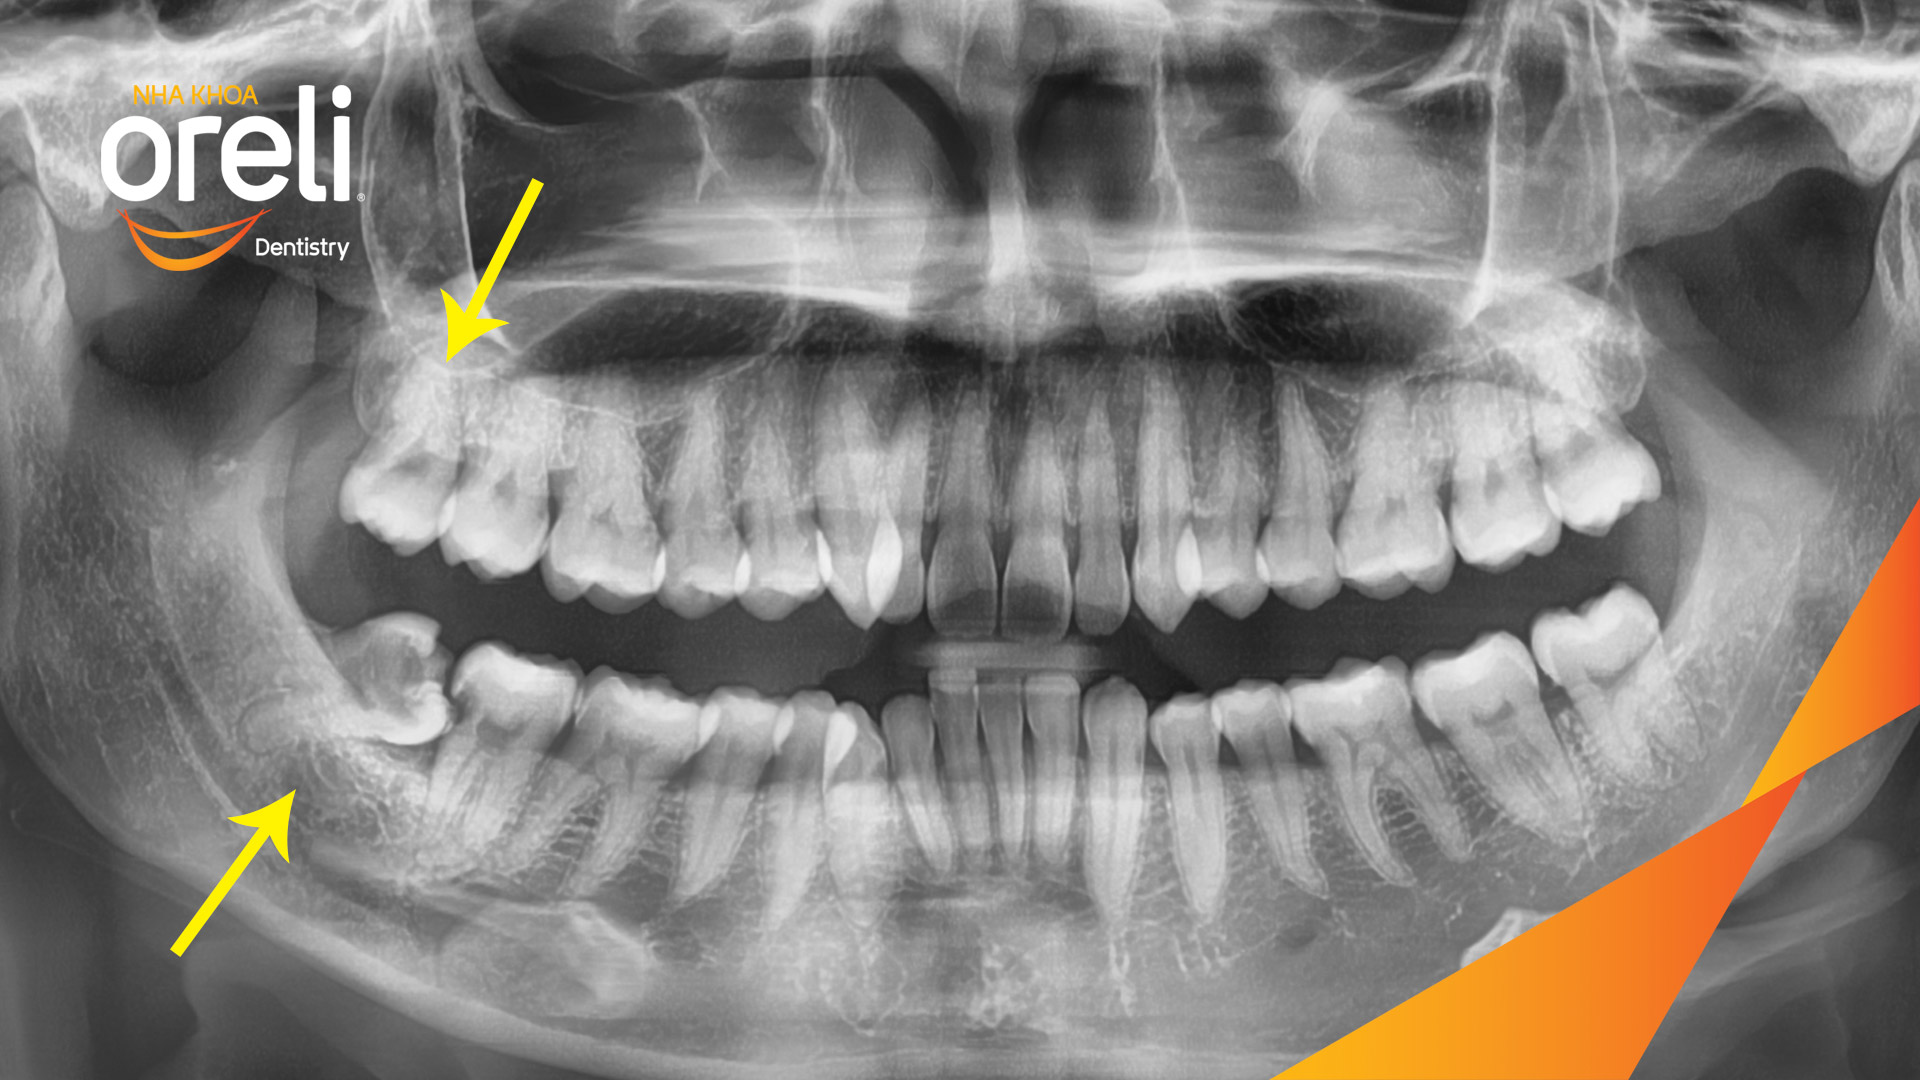

Nhổ răng khôn hàm dưới khó do mọc ngang – Case tại Oreli

Nhổ răng khôn

Mọc lệch

Xem thêm